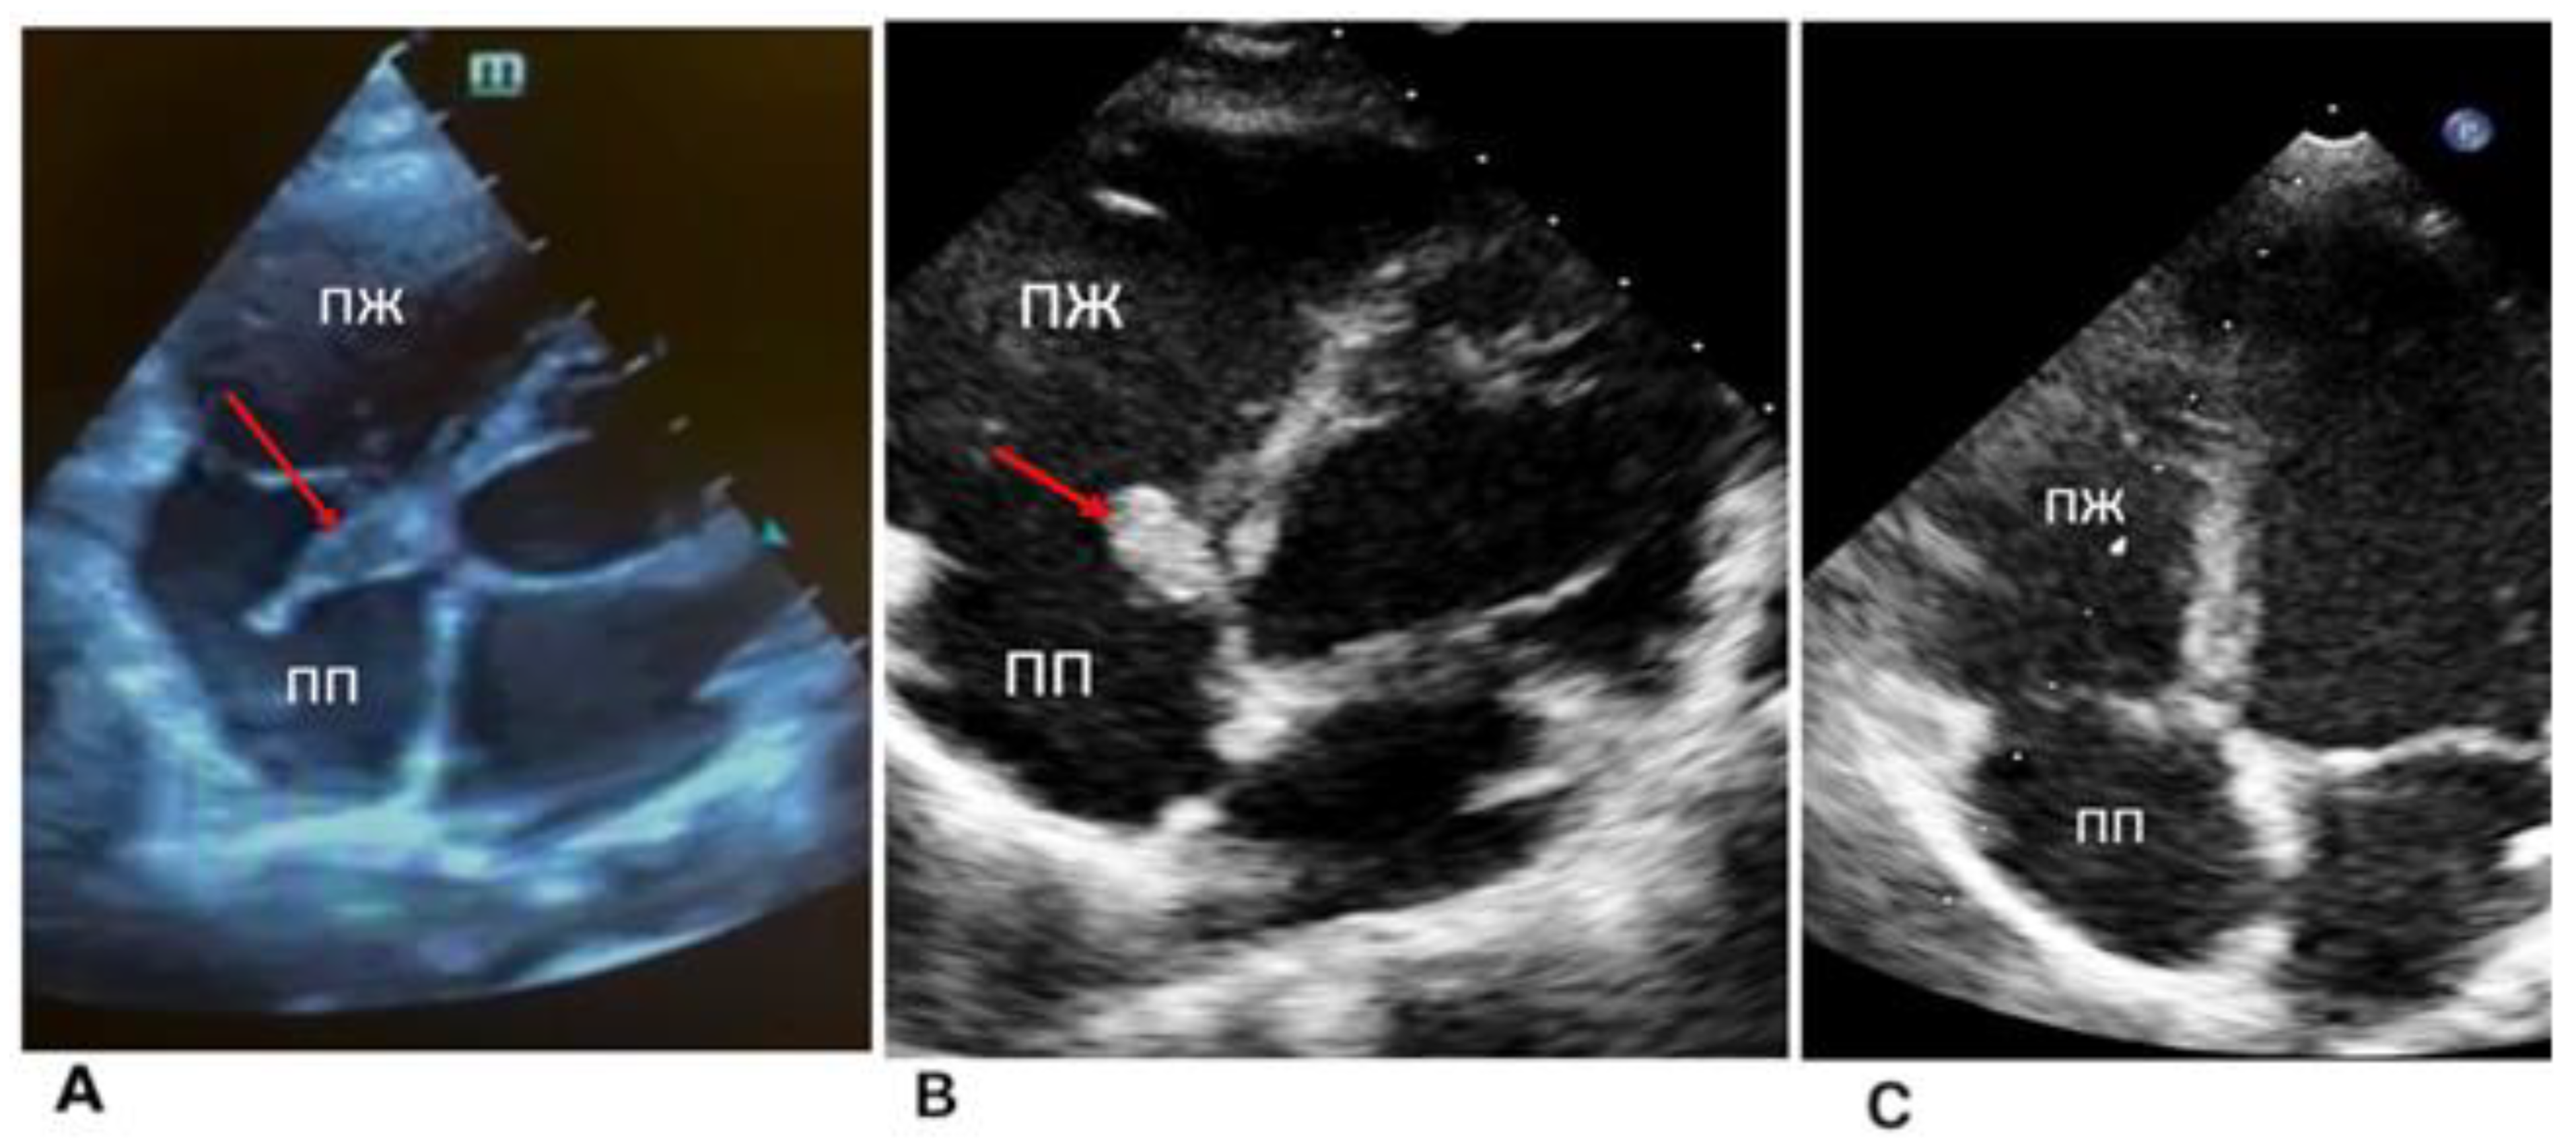

2. Case 1

2.1. Examination Data

2.2. Substantiation of Diagnosis

3. Case 2